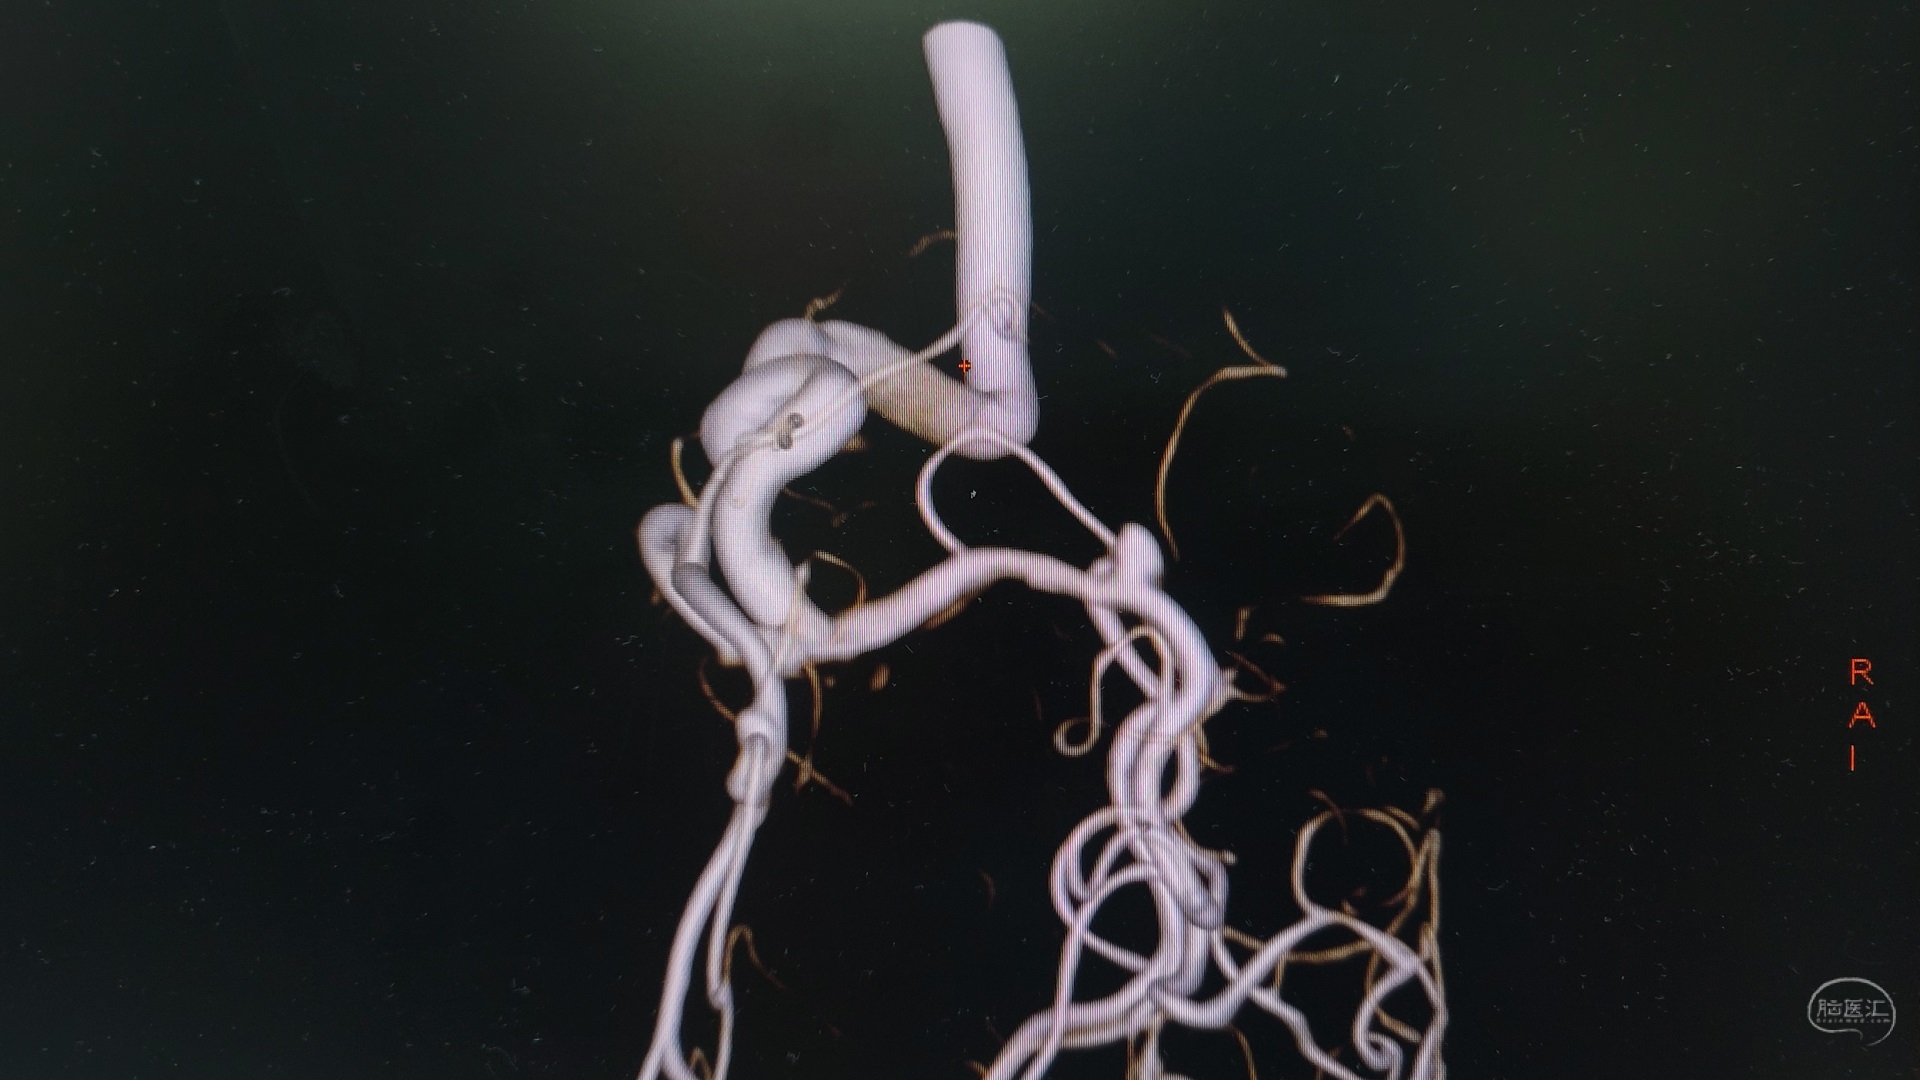

CTA显示大脑中动脉瘤消失,分支血管保留完好。

CTA显示A2/A3动脉瘤消失,近端分支血管保留完好。